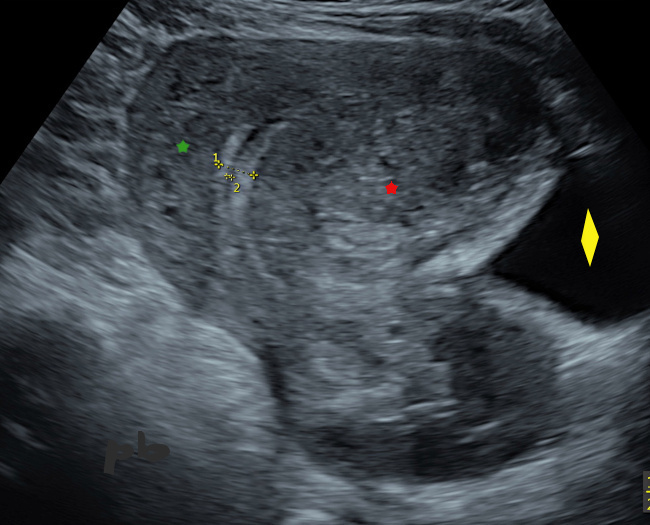

13- Adénomyome – Echo

Echo endovaginale centrée sur les 2 cornes utérines (★).

– à droite, pas d’épaississement myométrial. Visualisation du départ du trajet interstitiel de la trompe.

– à gauche, net épaississement, hétérogène, parsemé de petites images liquidiennes, formant une masse mal délimitée (►) : adénomyome.

Il n’y avait pas d’aspect d’encorbellement vasculaire en doppler couleur, au contraire de ce que l’on voit souvent dans les myomes.

13-Adenomyoma – Ultrasound

Transvaginal ultrasound focused on the two uterine horns (★).

– On the right, no myometrial thickening. Visualization of the beginning of the interstitial segment of the tube.

– On the left, clear heterogeneous thickening, dotted with small cystic images, forming a poorly defined mass (►) : adenomyoma.

There was no appearance of vascular crown on color Doppler, contrary to what is often seen in fibroids.